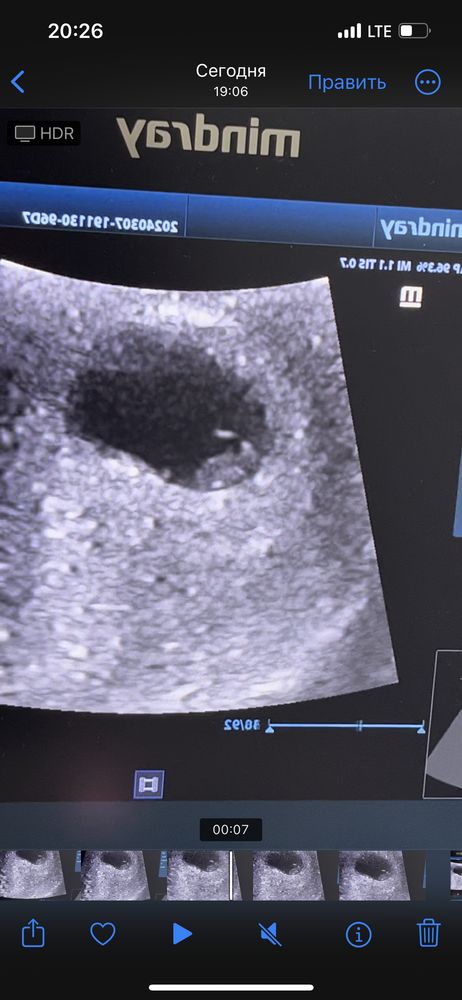

7 недель 2 дня

Ктр 9,9 мм

ЧСС 157